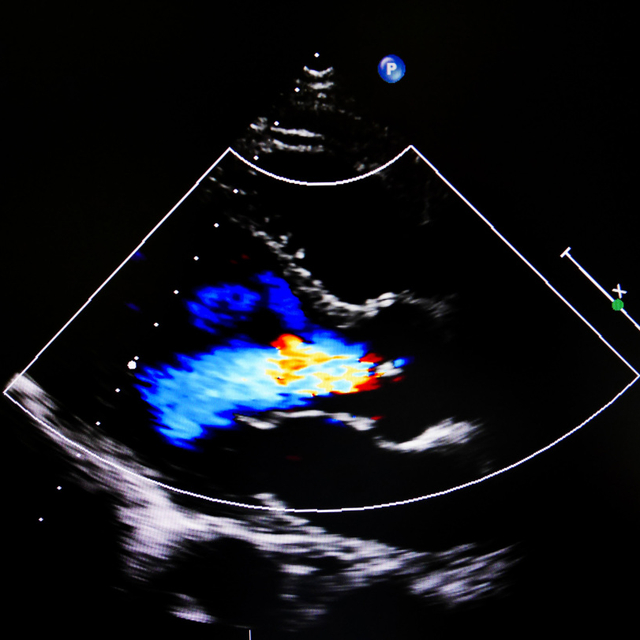

超声心动图是一种无创性的心脏检查方法,通过超声波探测心脏的内部结构和功能,可以观察到各个“房间”的大小、形态是否正常,“门窗”、“墙壁”是否完整,功能是否正常,它可以检测到心脏瓣膜是否正常工作,心脏壁是否增厚或变薄,以及心脏的收缩和舒张功能是否正常,能够直观地看到心脏的内部结构。在此基础上添加彩色多普勒,可以观察心脏的血流是否正常,评估心脏血流动力学,更加准确评估病情。形象地说,超声心电图就相当于雷达探测器,探测心脏结构是不是合理,墙壁稳不稳固,门是否关得严。